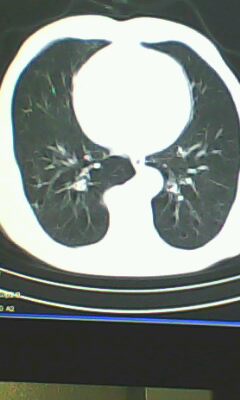

标题: CT26182:男 胸憋 无其它异常症状

胸廓呈桶状,双膈低平,肺实质及纵隔未见明显异常密度灶考虑肺气肿.

未见明显异常。

肺气肿

做个肺功能检查。肺ct无明显异常。

慢阻肺是临床诊断,未见明显异常。